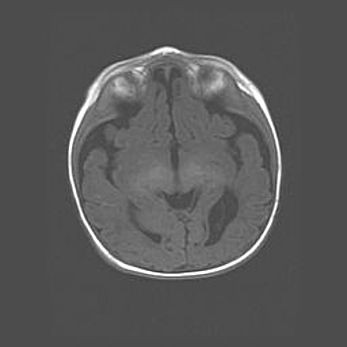

Аномалия Денди-Уокера. Признаки гипоплазии мозолистого тела.

Возраст: 5 месяцев 3 дня

Вес: 5550 г

Пол: мужской

Окружность головы: 39 см

Срок гестации: 40 недель

Аномалия Денди-Уокера – это порок развития головного мозга, для которого характерна триада симптомов: гипотрофия или аплазия червя мозжечка и/или полушарий мозжечка, расширение четвёртого желудочка с формированием ликворной кисты задней черепной ямки, гипертензионная гидроцефалия различной степени.

Гипоплазия мозолистого тела относится к дефектам внутриутробного этапа развития мозговой ткани, возникающим в процессе закладки структур головного мозга, что происходит на начальных этапах развития эмбриона.